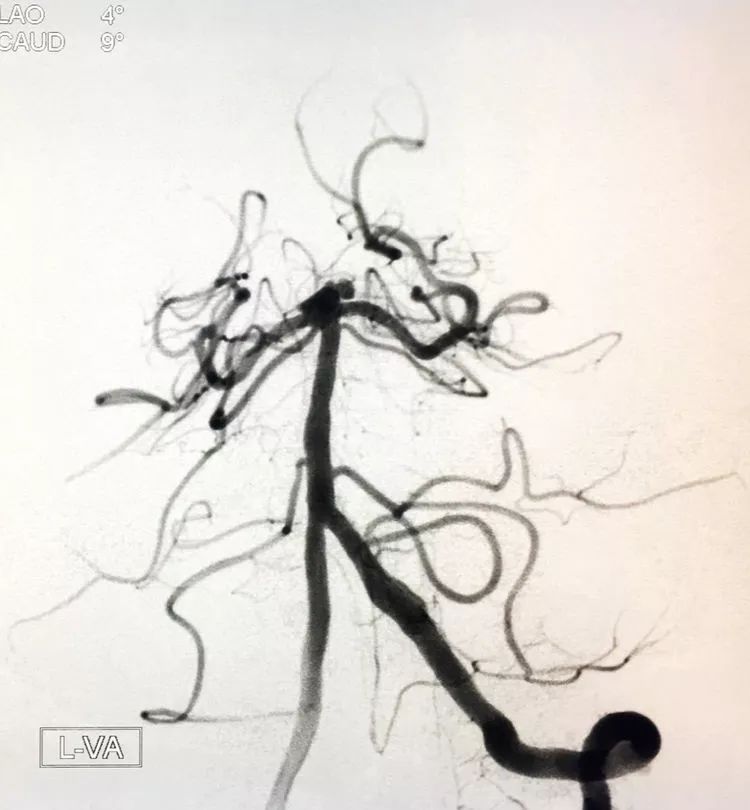

左椎动脉正位造影可以看到指向左方的子瘤。

术后左椎动脉正位、侧位的造影和蒙片